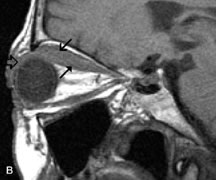

PATIENT PREPARATION Before MRI is performed, patients must be screened and prepared to avoid the potential hazards associated with the strong magnetic field. Patients who have ferrous aneurysm clips or cardiac pacemakers, who depend on life-support equipment, or who retain a possible metallic intraocular foreign body are not candidates for this imaging modality. MRI cannot be performed on obese patients who cannot fit into the bore of the magnet. Patients who are claustrophobic may not tolerate a prolonged period of study within the confines of the magnet, whereas others might do well if given a mild sedative. All worn metallic objects (e.g., necklaces, watches) should be taken off, credit cards set aside, and eye makeup removed before entering the room containing the magnet.5,20,34,35,36 NORMAL ORBITAL ANATOMY T1-weighted images provide the best anatomic details of the orbit because they display superior contrast resolution between normal structures (see Fig. 8). The vitreous has a long T1, resulting in an intermediate signal similar to brain, whereas the crystalline lens and sclera appear dark because of a longer T1 and short T2. The extraocular muscles, like all skeletal muscles, demonstrate a moderately long T1 and short T2 and highly contrast with the intense signal of the surrounding orbital fat (adipose tissue has an extremely short T1). The lacrimal glands appear as mottled areas of reduced intensity of the signal from the orbital fat in the lacrimal fossa. The optic nerves are seen with the same signal intensity as brain white matter and are hypointense relative to the orbital fat because their Tl is longer than the Tl of fat but shorter than the Tl of water. Cortical bone is not well delineated because it contains little free water, yielding minimal signal in MRI, and thus appears dark on all pulse sequences. This feature explains why MR images of the orbital apex and intracanalicular portion of the optic nerves are superior to comparable CT scans. Partial volume averaging of the bones in these regions obscures soft tissue details on CT images, whereas MRI reveals the signals only from the soft tissue structures with no cortical bone input. Bone marrow, on the other hand, is seen as a relatively intense signal because of its high fat content (see Fig. 8).37,38 T2-weighted pulse sequences are not ideal for imaging normal anatomy; however, they are particularly useful in revealing pathologic conditions (see Fig. 9). T2-weighted studies are most easily recognized by a bright vitreous signal. ORBITAL DISEASES Vascular Lesions Cavernous hemangiomas appear as well-circumscribed, smooth, usually intraconal masses that are isointense to muscle on T1-weighted images and hyperintense on T2-weighted images (Fig. 12). Patchy early enhancement is typically followed by diffuse, more homogeneous enhancement.39 The internal architecture of the mass, including septation and internal vasculature, may often be appreciated with high-quality orbital imaging.40 Lymphangiomas consist of ectatic vascular channels within a connective tissue stoma with varying degrees of lymphoid cellularity. On MRI, these tumors are typically poorly circumscribed, multicompartmental, and heterogeneous, often showing cystic dilations with fluid levels (Fig. 13). The signal characteristics within lymphangiomas vary considerably, reflecting cystic and solid components and the varying paramagnetic characteristics of blood at different stages of degradation.40–42 Acute hemorrhage appears hypointense on both T1- and T2-weighted formats. Methemoglobin present in subacute hemorrhage (3 to 14 days) leads to hyperintense signal on both T1- and T2-weighted images.41 A small percentage of lymphangiomas appear radiologically indistinct from orbital cavernous hemangiomas.43 Orbital varices are venous malformations that expand with increased systemic venous pressure, such as with Valsalva maneuvers. Because rapid acquisition of images during a Valsalva maneuver is important in imaging such a lesion, conventional or spiral CT is currently the modality of choice.44 MRI is an excellent modality for demonstrating enlargement of the cavernous sinus and dilation of the superior ophthalmic vein in patients with high-flow carotid-cavernous fistulas (Fig. 14).37MRA may be helpful in the evaluation of the venous outflow pattern. The rapidly flowing blood in these vascular structures carries the excited protons out of the section before they can be imaged, resulting in their dark appearance.5 In low-flow dural arteriovenous malformations, MRA may help define the arterial feeding vessels.45 Neural Lesions MRI is more effective than CT in delineating the intracranial optic nerves, chiasm, and optic tracts and, for this reason, is the preferred imaging modality in the evaluation of optic nerve disorders. The spatial relationships and image contrast of the orbital tissues with intraorbital optic nerve tumors is comparable between the two imaging modalities. The normal nerve is isointense to brain and appears enlarged and kinked owing to infiltration of an optic nerve glioma on T1-weighted images. Gliomas appear hyperintense on T2-weighted images and may be heterogeneous owing to cystic areas within the tumor. Contrast enhancement is variable.46 Intraorbital and intracranial optic nerve sheath meningiomas are usually isointense to cortical gray matter on Tl-weighted images and remain isointense on proton density studies (Fig. 15). Gd-DTPA is useful in delineating the intracranial extension of optic nerve meningiomas.7,47 The hyperostosis of bone and calcification associated with meningiomas are not demonstrated as well on MRI studies as on CT scans.20,37 Gd-DTPA–enhanced MRI also appears promising in the study of the permeability of the blood–brain barrier in selected optic neuropathies.22,48 MRI may reveal an enlarged optic nerve and some degree of contrast enhancement in cases of optic neuritis.49 Muscle Disorders Extraocular muscle enlargement in patients with thyroid-associated orbitopathy is demonstrated equally well with CT and MRI studies. However, the superior tissue contrast on MR images reveals better details of the relationships of the optic nerve to the thickened muscles at the orbital apex (Fig. 16).50 In addition, MRI may be able to differentiate between muscles that are enlarged as a result of edema and active inflammation and those enlarged because of fibrosis by their T2 relaxation times.21 Quantitative MRI was not found to be accurate in predicting the success of low-dose orbital irradiation.51 However, a muscular index relating the diameters of the rectus muscles to the bony orbital dimensions was useful in predicting optic nerve compression.52 MRI is also effective in imaging orbital tumors of mesenchymal origin, such as rhabdomyosarcoma, particularly in the assessment of extension into the anterior and middle cranial fossae (Fig. 17).37 The lack of any pathognomonic radiologic features necessitates rapid orbital biopsy when rhabdomyosarcoma is suspected. Osseous Lesions In general, CT is the imaging modality of choice when details of quantity and quality of bone are needed; however, abnormalities of bones can be detected indirectly by MRI. Cortical bone appears black (signal void) on MR images because of its low proton density and free-water content. The absence or discontinuity of the signal void of the orbital walls may represent bony destruction or fracture. Hyperostosis associated with prostate metastases or meningioma is visualized as areas of black smudging.50,53 Diseases in which the bone is replaced by pathologic tissues with a high free-water content, such as fibrous dysplasia, are well demonstrated on MRI. An intermediate signal intensity on T1-weighted images and hypointense signal on T2-weighted images is representative of fibrous dysplasia. Enhancement on post–Gd-DTPA MR scans is seen and is more evident in areas that are less mineralized.54 Cystic Lesions Dermoid cysts appear as rounded, well-defined lesions typically contiguous with an orbital bony suture. The high-intensity signal on T1-weighted images is attributed to the sebaceous-produced lipid contents (Fig. 18).31,50 Mucoceles may demonstrate a hypointense or hyperintense signal on MR images, depending on the concentration of proteinaceous or inflammatory fluid components. The integrity of the bony walls of the expanded sinus cavities cannot be assessed on MR as well as by CT.37,50,55,56 A high-signal intensity on Tl- and T2-weighted images is characteristic of orbital chronic hematic cysts because of the blood-breakdown products within the cysts.57 Trauma Although soft tissue relationships are usually better demonstrated on MRI, the evaluation of craniofacial bony trauma is preferable with CT. For example, prolapse of orbital fat through a fracture site and hemorrhage of adjacent tissues are demonstrated in an MR image, but the actual fractured bone is not imaged. Three-dimensional MRI of the orbit in subacute trauma has been described,58 although its precise role is not currently established. MRI has been suggested to be superior to CT in detecting intraorbital wooden foreign bodies.59,60 In a series of penetrating orbital injuries with organic foreign bodies, however, MRI was able to identify the foreign body in only four of seven cases.61 With an in vitro model for wood foreign body, McGuckin and colleagues concluded that CT was the imaging modality of choice.62 A careful history and, in selected cases, plain films to rule out a metallic foreign body are crucial before MRI is considered in patients with periocular trauma. MRI is particularly helpful in the detection and characterization of subperiosteal hematomas of the orbit (Fig. 19). They are most commonly seen in the subperiosteal space of the superior orbit as well-defined masses following a traumatic injury. The signal intensity varies depending on the acute, subacute, or chronic nature of the hematoma, based on the stage of blood degradation. Fresh hemorrhages are hypointense on T1-weighted images and hyperintense on T2 images. Hematomas that are 1 to 7 days old are hypointense on both T1- and T2-weighted images. T1-weighted images of hematomas more than a week old are hyperintense due to the oxidation of deoxyhemoglobin to methemoglobin, whereas the T2 images remain hypointense.63 Metastatic Tumors Breast carcinoma metastatic to the orbit has been demonstrated to be hypointense to the surrounding orbital fat on T1-weighted studies and hyperintense on T2-weighted images and has an affinity to the extraocular muscles (Fig. 20).50,64 The MRI characteristics of prostate carcinoma metastatic to the orbit have been described as involving the greater and lesser wing of the sphenoid, orbital roof, and optic canal. Diffuse bone hypertrophy with isointense or slightly hyperintense tissue on T1-weighted images represents the osteoblastic carcinomatous bone infiltration. Contrast enhancement is variable on T1-weighted and fat-suppressed images.65 Most other metastatic tumors also have a lower intensity signal on T1-weighted images and appear to displace or infiltrate normal orbital structures; however, their signal characteristics are variable on T2-weighted MR images.66 Many metastatic tumors demonstrate bright contrast enhancement with Gd-DTPA. Infectious Disorders MRI findings of preseptal and orbital cellulitis typically include increased signal intensities on T2-weighted images of the eyelids and orbital fat, respectively, due to the increased water content of the tissues. Since most cases of bacterial orbital cellulitis are associated with paranasal sinusitis, hyperintense signals of the affected sinuses may also be found on T2-weighted images as well as enhancement of polyps and granulation tissue on postgadolinium T1-weighted MR images. Subperiosteal abscess formation may occur due to contiguous spread of infection from the paranasal sinuses and appear on MRI as an area of intermediate signal on T1-weighted and proton-weighted MR images. The abscess may appear slightly hyperintense compared with muscle on T2-weighted scans with the necrotic contents having the greatest intensity.67 MRI and MRV are more sensitive than CT in revealing cavernous sinus thrombosis. Engorgement of the cavernous sinus, extraocular muscles, and ophthalmic veins is seen with hyperintensity of the thrombosed sinuses evident on all pulse sequences. The enlarged, thrombosed superior ophthalmic vein appears less hypointense than the normal contralateral ophthalmic vein, and hyperintensity within the lumen of the vessel may be seen on T1- and T2-weighted MR images.68 Inflammatory and Lymphoproliferative Lesions Inflammatory conditions of the orbit, both idiopathic (inflammatory pseudotumor) and those of known causes, have been found to be hypointense to fat and isointense to muscle on Tl-weighted studies and isointense or slightly hyperintense to fat on T2-weighted images (Fig. 21).50,64,69 The more fibrous or sclerosing varieties have less signal intensity on T2-weighted images. Marked enhancement is seen in pseudotumor infiltrates after gadolinium administration.70 The same signal characteristics are demonstrated in patients with Tolosa-Hunt syndrome, with mass lesions seen in the cavernous sinuses and orbital apices.71 Lymphomas have MRI characteristics similar to those of inflammatory lesions in that they are hypointense to fat and isointense to muscle on T1-weighted images (Fig. 22). They may appear hyperintense to fat on T2-weighted images, perhaps owing to less fibrosis than that seen in orbital inflammatory pseudotumor, although this is not a consistent finding.31,50,66 Lymphoid tumors typically enhance moderately after contrast injection. Unfortunately, studies have shown that tumor density and homogeneity are similar between inflammatory and malignant orbital infiltrates, and MRI cannot differentiate these lesions.72,73 Lacrimal Gland Tumors Lacrimal gland lesions present special problems in diagnosis and management. Pleomorphic adenoma (benign mixed tumor) should not be biopsied, but rather excised in toto. On the other hand, for lymphoma and inflammatory infiltrates, incisional biopsy is more appropriate than complete excision of the lacrimal gland. Thus, preoperative clinical and radiologic evaluation are especially crucial in planning appropriate surgical management. Pleomorphic adenomas demonstrate long T1 and T2 signal characteristics. They may show heterogeneity on T2-weighted images74 and moderate to marked enhancement with contrast.75 Signal characteristics of adenoid cystic carcinoma include hypointensity to fat on T1-weighted images, hyperintensity to fat with increased T2 weighting, and isointensity to fat on proton density-weighted studies (Fig. 23).31,75 Secondary bony alterations of the lacrimal fossa associated with lacrimal gland tumors, such as remodeling (benign mixed tumor) or destruction (adenoid cystic carcinoma), are seen indirectly on MR images; however, bone windows on CT scans provide better delineation of these changes. In contrast to the round or globular appearance of benign or malignant epithelial tumors of the lacrimal gland, lymphoproliferative tumors usually appear to be molding or draping onto the globe and the surrounding bony orbit. LACRIMAL DRAINAGE SYSTEM DISORDERS MRI with surface coils provides excellent spatial resolution and tissue-specific signal intensities of the lacrimal drainage system. These parameters have been found useful to more accurately demonstrate the extent of lesions in the lacrimal sac and differentiate long-standing mucoceles from solid tumors than CT.76 Physiologic studies in patients with tearing disorders now include MR dacryocystography, in which Gd-DTPA is either placed topically in the conjunctival fornix or injected by cannulation into the lacrimal sac. They provide a detailed morphologic and functional analysis of the lacrimal excretory system; however, they are no more sensitive than digital-subtraction dacryocystography or CT dacryocystography.77–79 INTRAOCULAR TUMORS On MRI, uveal melanomas have a typical appearance that helps to differentiate them from other primary and secondary intraocular tumors as well as choroidal detachments. Pigmented melanomas are hyperintense on Tl-weighted images, hypointense on T2-weighted studies, and hyperintense on proton density–weighted examinations (Fig. 24).30,31,50,80–82 These signal characteristics have been attributed to the paramagnetic properties of melanin because of stable free radicals that shorten the T1 and T2 relaxation times. Moderate enhancement is seen on postgadolinium T2-weighted images. Gadolinium-enhanced T1-weighted images are particularly sensitive in detecting choroidal melanomas.83 MRI may be less sensitive in detecting extrascleral extension of tumor than echography performed by an experienced ultrasonographer.84 Tumors metastatic to the choroid are hyperintense on T1- and T2-weighted images.24 The signal characteristics, however, may be similar to those seen with choroidal melanoma. Choroidal hemangiomas, on the other hand, have an intermediate signal on T1-weighted sequences and become hyperintense on T2-weighted images50 as well as proton density–weighted images.81 Retinoblastomas display moderate signal intensity on T1-weighted studies and a low signal on T2-weighted images.31,80,85 Calcification can be easily detected by CT and ocular ultrasonography but is not imaged by MRI.25,50 The presence of optic nerve involvement is best evaluated by MRI. ACQUIRED ANOPHTHALMIA When an eye is removed owing to tumor or trauma, an implant is typically placed in the intraconal space. MRI may be useful in defining the size, shape, and position of such orbital implants.86 Porous hydroxyapatite or polyethylene implants are preferred by many surgeons performing enucleation or evisceration. A porous implant offers the possibility of supporting a motility coupling peg to increase the movement of the overlying prosthesis. MRI with contrast is used by some surgeons to evaluate the degree of fibrovascular ingrowth in hydroxyapatite87 and porous polyethylene88 implants prior to motility peg placement. |